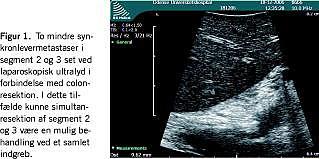

Spørgsmålet om, hvorvidt simultanresektion af synkronelevermetastaser bør udføres, kan således ikke besvares evidensbaseret. SIR er muligt at udføre, og specielt hvis en mindre radikal leverresektion er mulig (Figur 1 ). I case-kontrol-studier har man påvist, at SIR kan udføres med lav morbiditet og mortalitet.